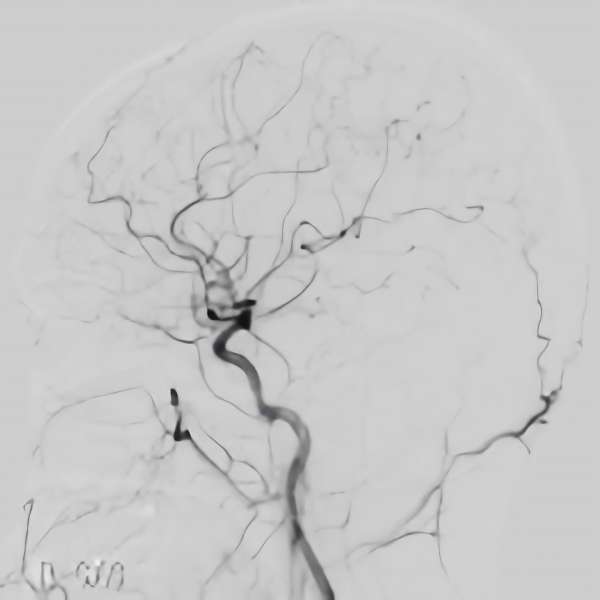

脳血管撮影

手術前

手術後